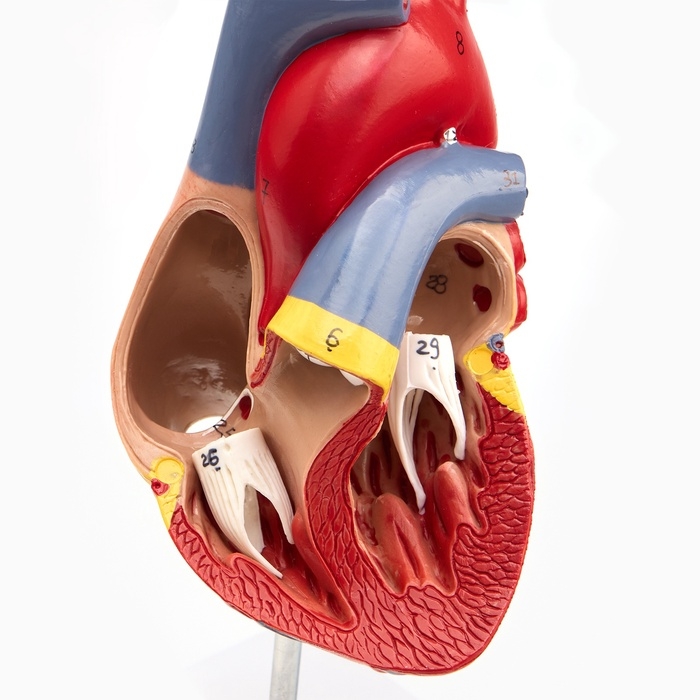

Анатомические модели

ЕКБ 93

No Brand, артикул: 7072363